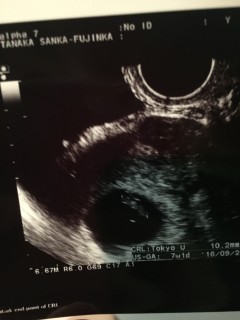

心拍も確認できました◎ 赤ちゃんの大きさは11.2mmとのこと。 前回、8wになっても胎嚢しか確認できず9wで稽留流産だったので、赤ちゃんの姿が見えて心臓が動いているのを見た瞬間思わず涙が溢れました(;_;) 先生から良かったですね、よく頑張りましたね、と言われてまた泣けてきました。 小さくてとてもとても可愛かったです!!